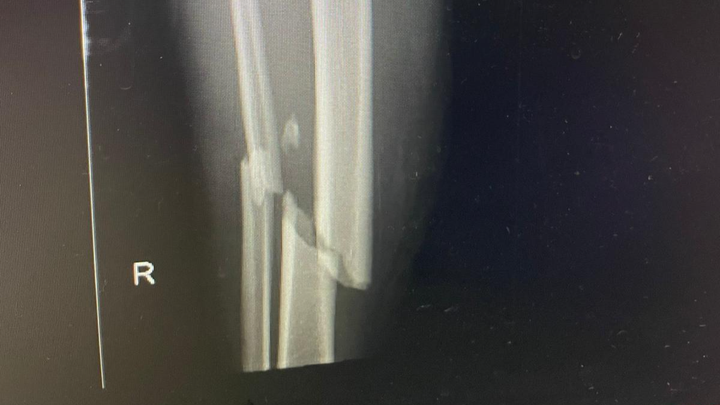

Hi. We are Park Row Rangers FC, we played in a friendly this morning, 1st June and one of our players was on the end of a tackle that has caused a broken leg. This is going to keep him out of work for multiple weeks, been told 6-8 months but that may be shorter. We are trying to raise as much funds as possible to help him out while he can't work.